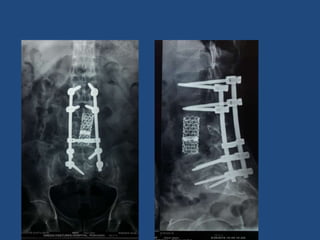

ISTHMIC LISTHESIS

Developmental High Grade Listhesis

Special Instruments